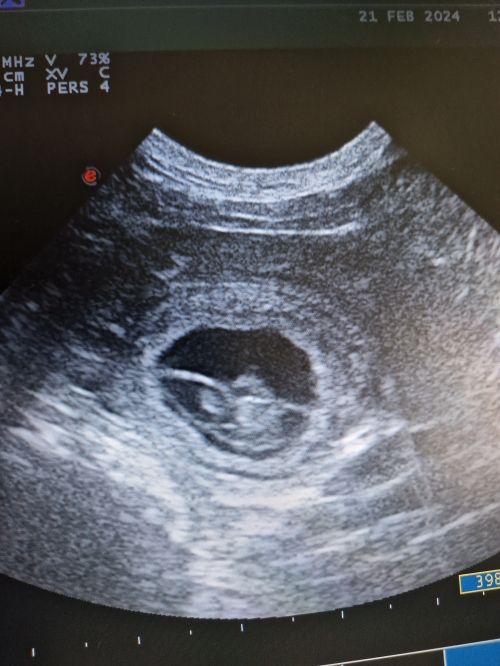

Tag 27 nach dem ersten Kontakt mit Ray dann die Überraschung, auf dem Bildschirm vom Ultraschallgerät können wir ganz deutlich kleine Fruchtblasen und am allerbesten: Kleine klopfende Herzchen ♥️ sehen.

Das Wunder hat begonnen: Unsere Cooki wird Mama🥰🥰🥰